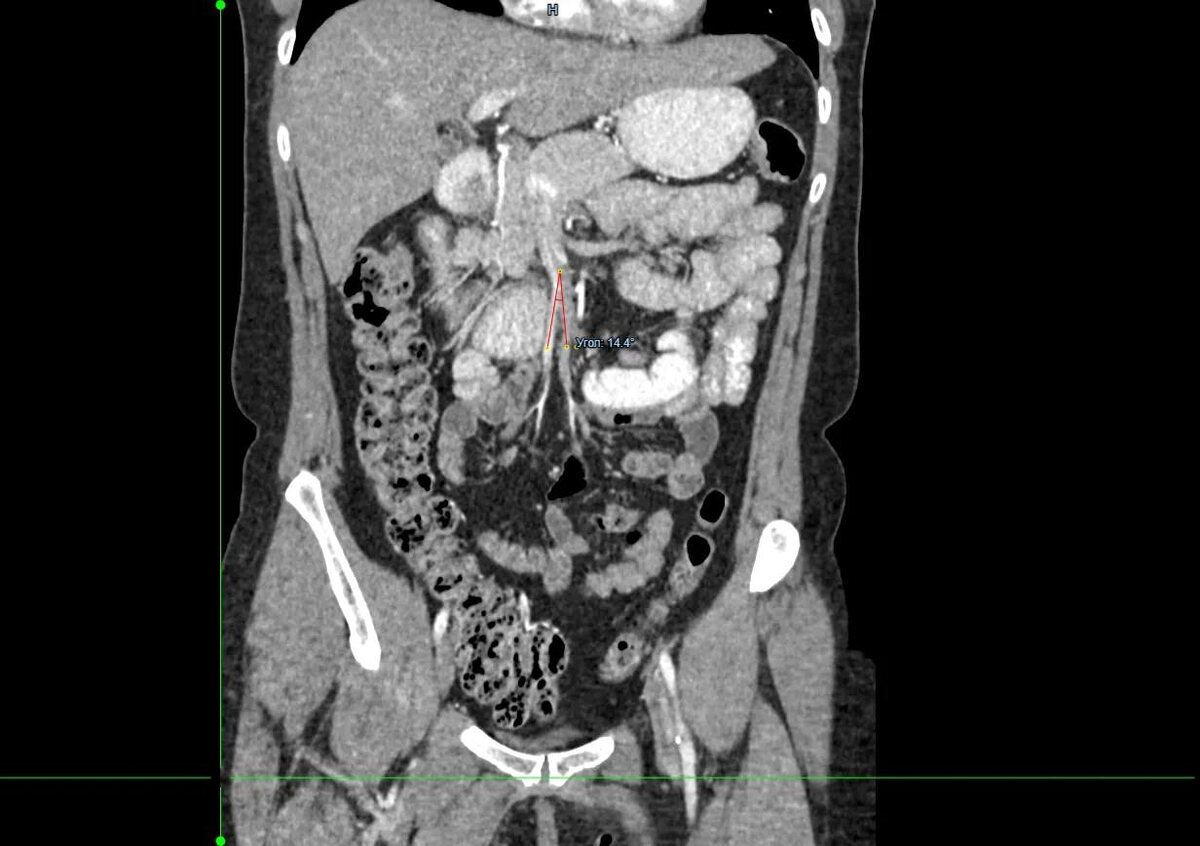

«Не могла нормально питаться»: хирурги прооперировали красноярку с редким заболеванием

Врачи хирургического отделения №3 Красноярской межрайонной клинической больницы №20 им. И.С. Берзона провели операцию 49-летней пациентке с синдромом Уилки. Из-за него женщина долго не могла нормально питаться и сильно похудела.